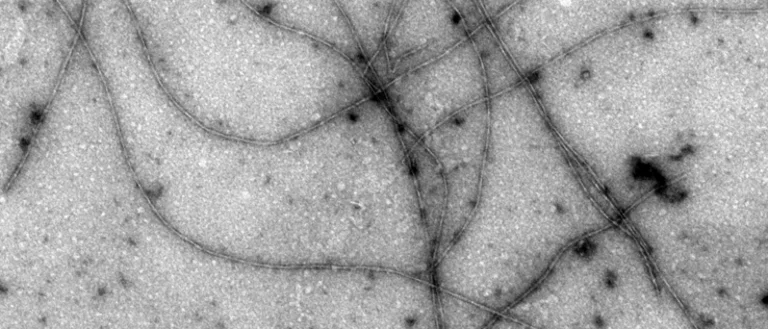

The Teplow laboratory seeks to understand and treat diseases associated with the aging process. These include Alzheimer’s disease (AD), Parkinson’s disease, Huntington’s disease, and Lou Gehrig’s disease. The laboratory has special expertise in AD, the most common cause of late-life dementia. A key cause of AD is thought to be a protein called the amyloid beta-protein (Abeta). This protein deposits in the brain to form what are called “amyloid plaques." Our group has worked to understand how these plaques form and to use this knowledge to design drugs to prevent or treat the disease. Our studies have revealed that Abeta shares properties with other proteins linked to human diseases of aging, therefore the work done on AD is likely to advance efforts to understand and treat these disorders.